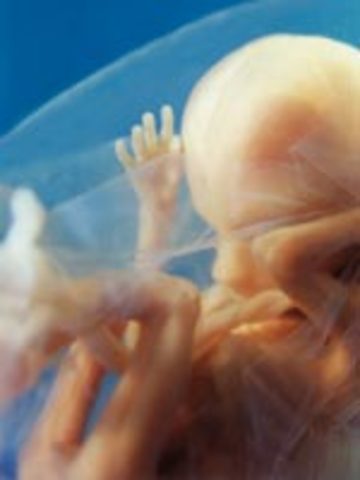

• Week Nine Developments

Week Nine Developments

The embryo's limbs are beginning to lose their tadpole-like look and start to form hands, feet, and touch pads. Organs and nerves are beginning to function.

• Week Ten Developments

Week Ten Developments

The fetus's total weight is about 1/3 of an ounce. The heart is almost completly formed and the placenta is mature enough to support the production of hormones.